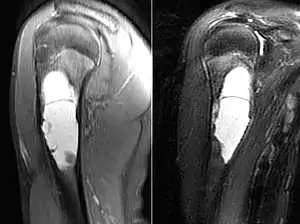

| MRI scan: simple bone cyst humerus of a 13 year old boy | |

Magnetic Resonance Imaging (MRI)

Magnetic resonance imaging scans are used to identify the precise location of the cyst, to see how aggressive the disease is, and to determine the actual shape and size.[4] The MRI uses a combination of magnets and radio-frequencies to produce various detailed, computerized images of the cyst and its surrounding body structures.[4]